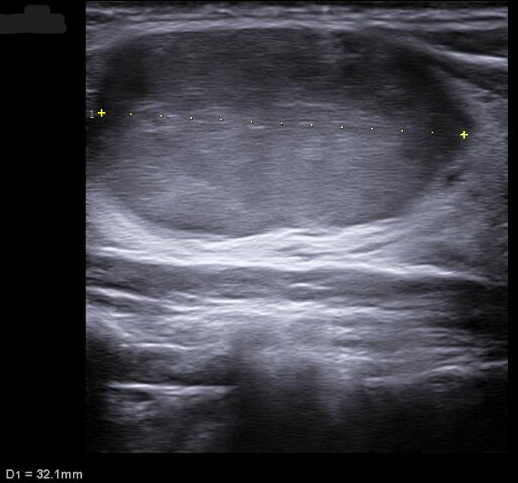

Ecografía tiroidea en AP: En lóbulo tiroideo derecho se aprecia nódulo: hipoecogénico, sólido, con márgenes definidos, sin focos ecogénicos, que presenta vascularización periférica, de morfología ovoide y de dimensiones 32x17x19 mm aproximadamente (CCxAPxT, más alto que ancho). Compatible con TIRADS 4.